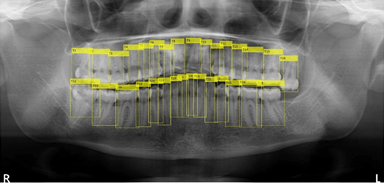

従来、歯科医院ではパノラマレントゲンの撮影後、歯科医師が目視で患者の歯牙情報をカルテや患者管理ソフトに入力し、診査・診断等を行っていました。本システムは、パノラマレントゲンの画像データから歯牙情報の有無をAI技術で自動解析し、また解析後の歯牙情報をアウトプットするものです。

本技術(特許出願中 出願番号:特願2020-132917)は、Springer Nature社のScientific Reportsに2020年11月6日付けで掲載された論文「Optimization Technique Combined with Deep Learning Method for Teeth Recognition in Dental Panoramic Radiographs」に基づきます。